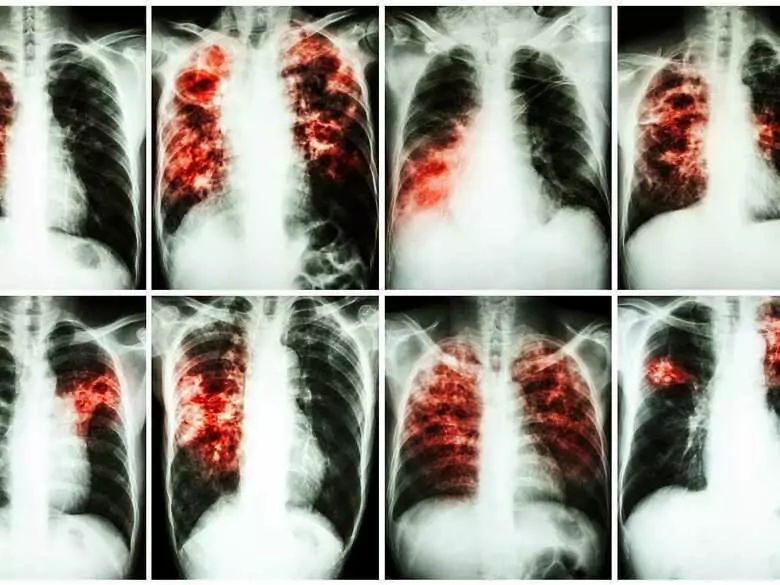

Forscher der medizinischen Fakultät Hradec Králové der Karlsuniversität in Prag haben ein neues Medikament gegen Tuberkulose erfunden. Das Medikament ist an ein amerikanisches Pharmaunternehmen verkauft worden, das es vertraglich weiterentwickeln wird. Die Prager Universität wird jedoch finanziell an den Erlösen aus dem Verkauf des Medikaments beteiligt.